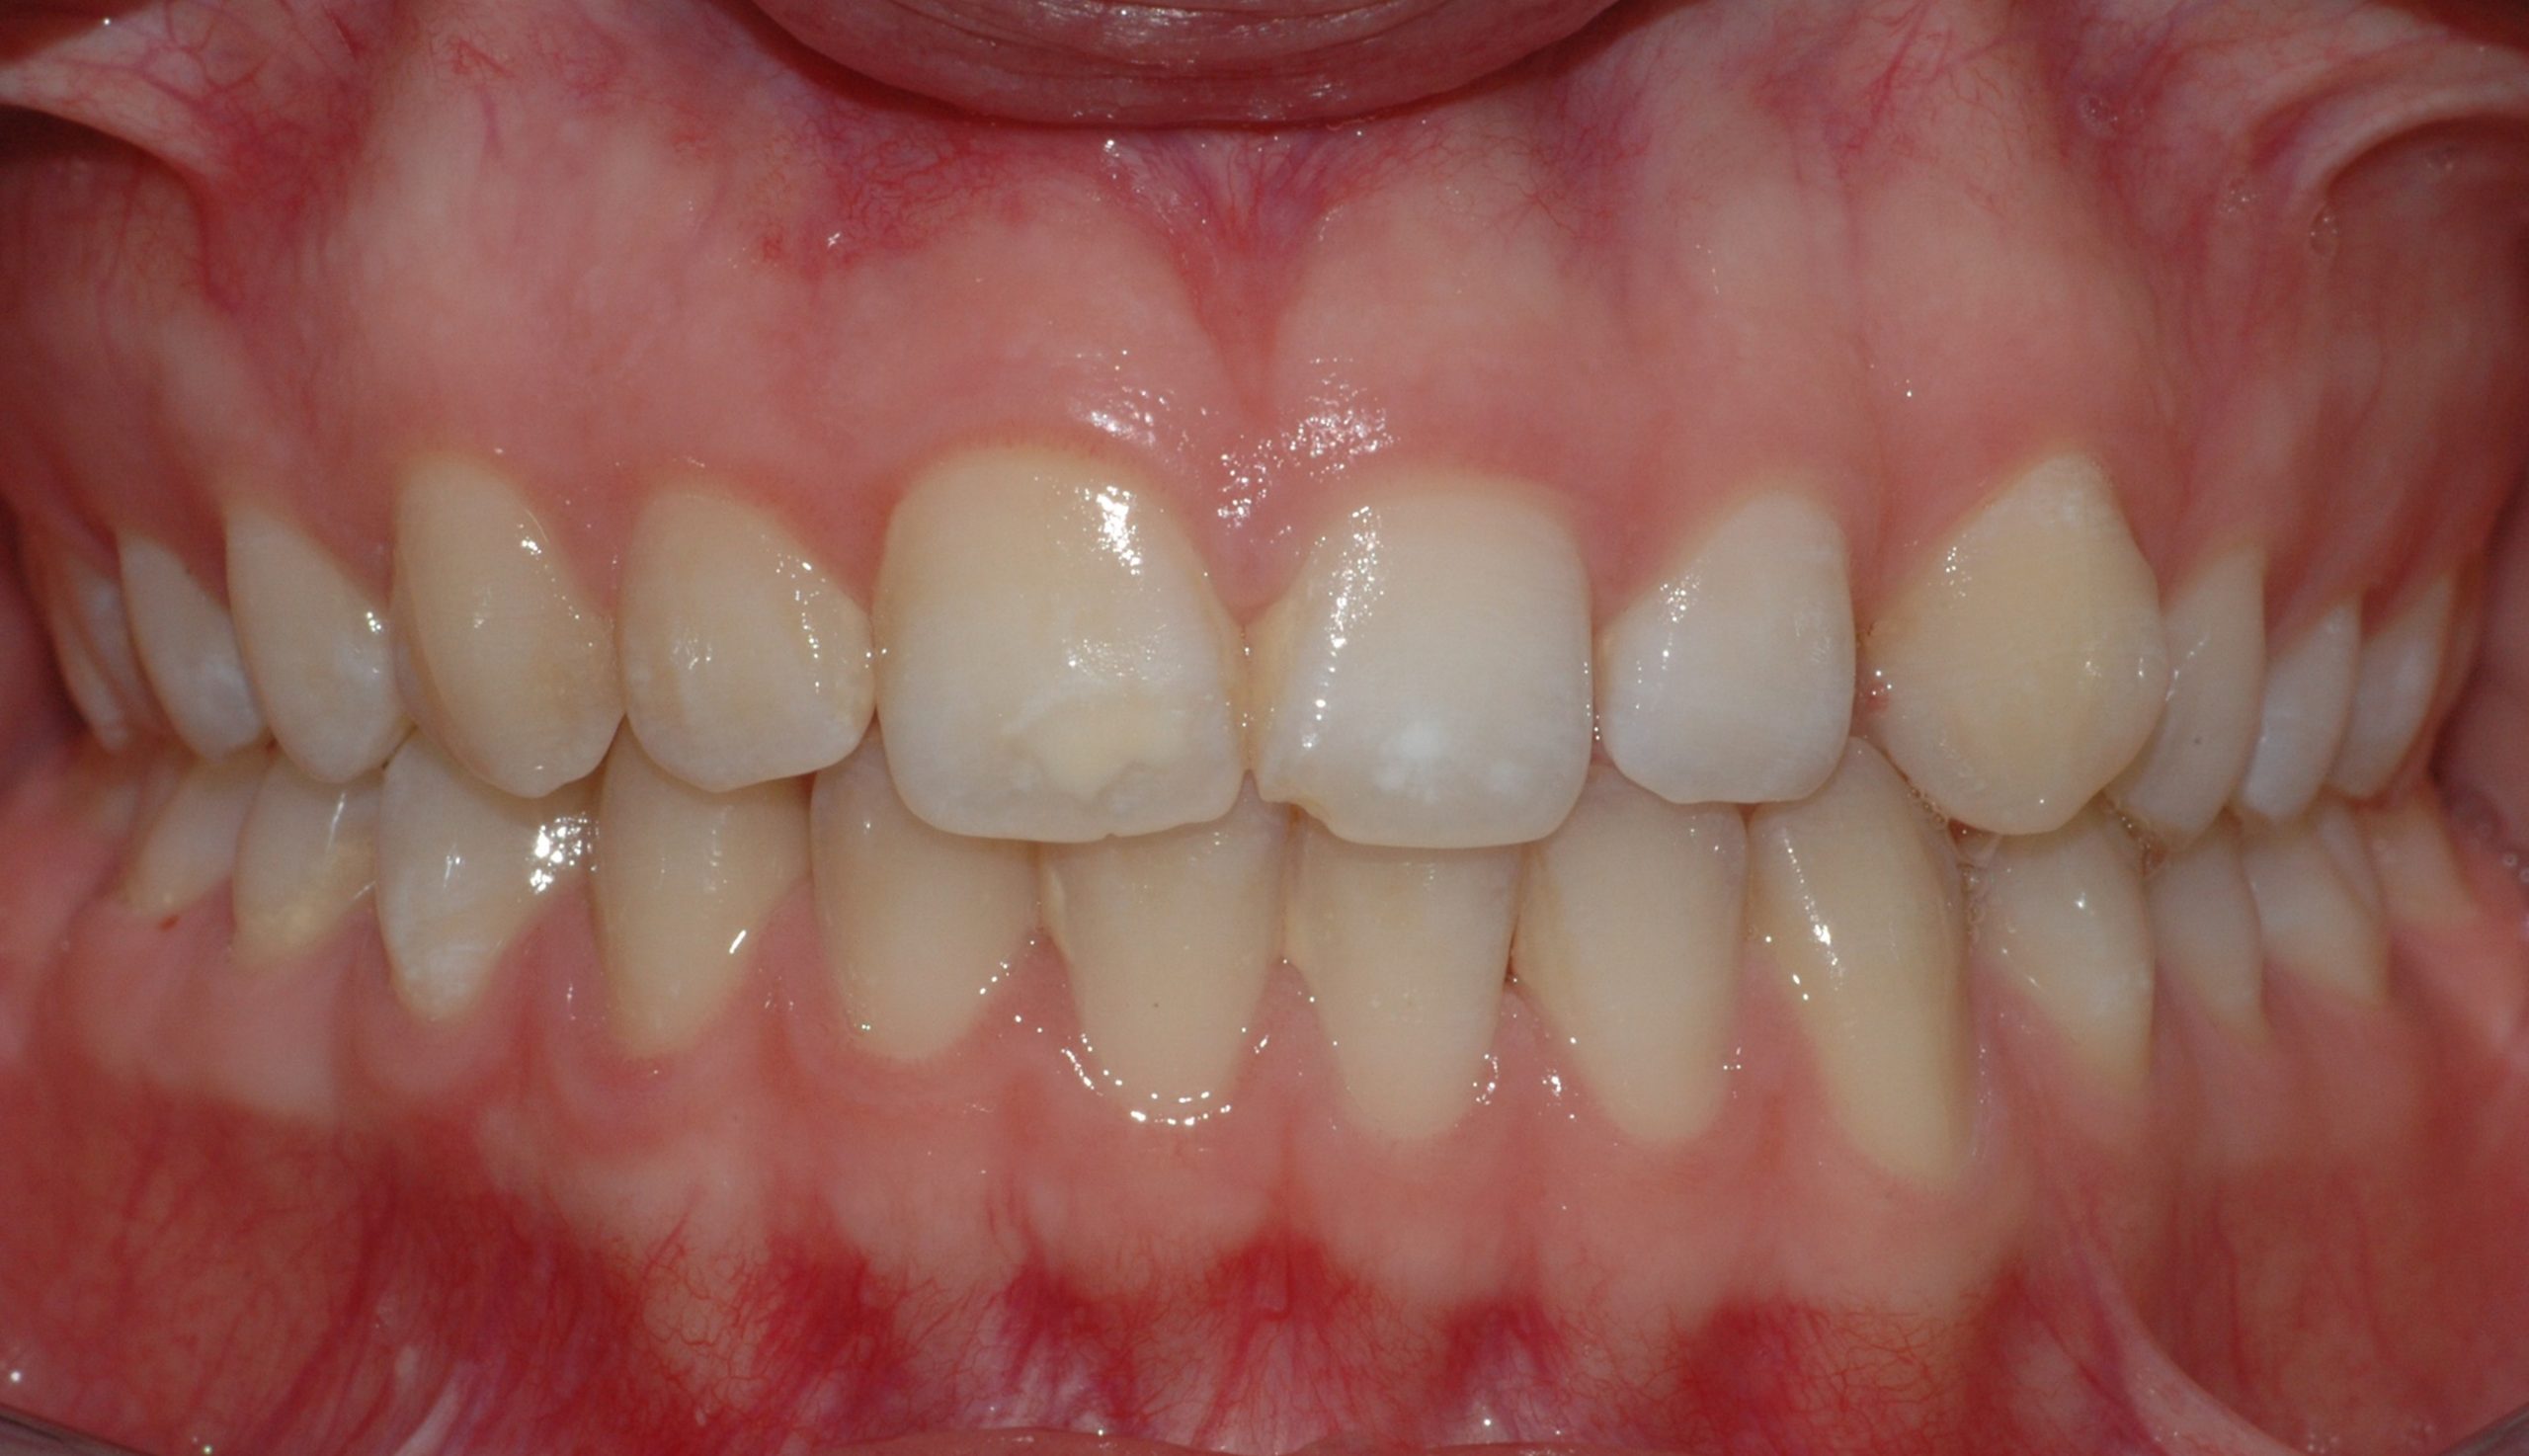

Caso clinico

La paziente si presenta a causa del malposizionamento del canino superiore di sinistra, ruotato lungo il suo asse di quasi 90 gradi. In seguito ad un trattamento con allineatori trasparenti di circa 7 mesi, il dente è stato portato in posizione assolutamente idonea.

La paziente si presenta con la richiesta di chiudere il diastema presente tra gli incisivi superiori, sia per motivi estetici, sia a causa di una forte infiammazione gengivale provocata dall’intasamento alimentare (food impaction) nello spazio aperto. In 6 mesi di tempo, il trattamento tramite allineatori, ha chiuso lo spazio e risolto il problema a livello gengivale.